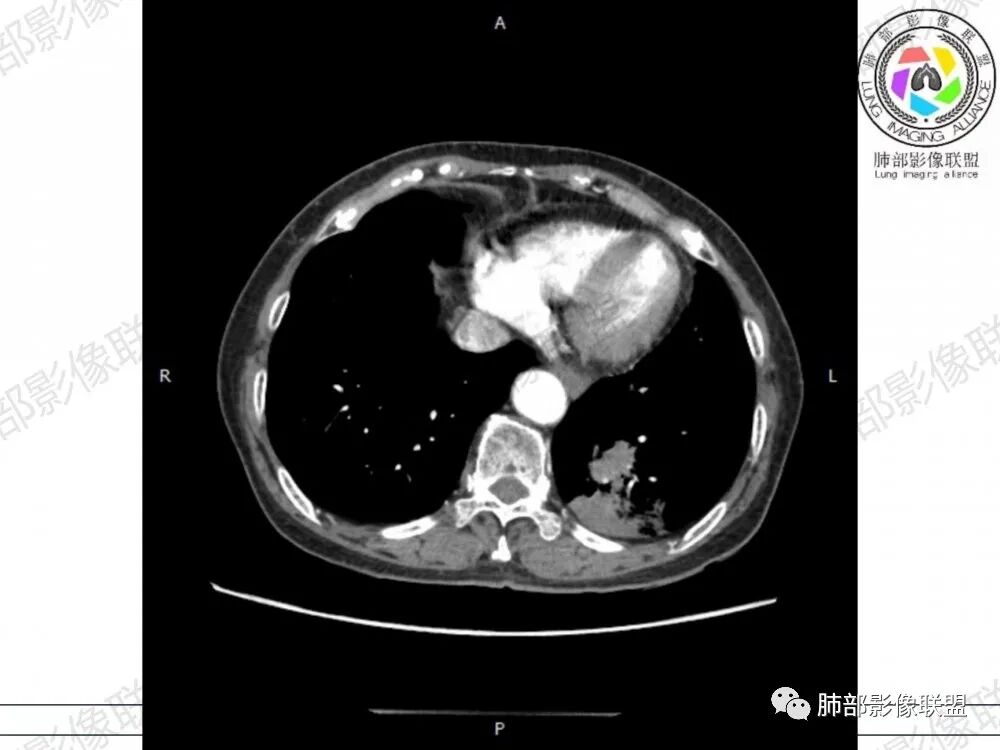

胸CT:左下叶胸膜下大片斑片影,长轴沿胸膜分布,实变、GGO混杂,磨玻璃边界清晰,粘液密度,小叶内间隔增厚,支气管进入后堵塞(枯枝),增强轻中度强化,血管造影征。常规考虑:肺腺癌?淋巴瘤?鉴别不典型病原体感染。

2、影像表现:无肺气肿背景,病变定位于左肺下叶背内侧基底段,病灶呈不规则团块影,靠近胸膜侧,其内密度不均匀,内见空洞、实变及磨玻璃影,磨玻璃影呈碎石路征,边界清楚,实性肿块边界膨隆,其内见空洞。空洞周围比较实。病灶较大的支气管通畅,细小的支气管成“枯枝征”。无胸膜增厚及胸膜腔积液,增强扫描呈中度强化,见血管造影征。

2、典型的粘液腺癌,收缩力很弱,肺泡壁断裂常有,张力存在,早期较少出现张力表现,破坏力偏弱,支气管与肺血管大多保留,所以增强病灶内见强化血管影(血池),也是粘液腺癌另一个特点。